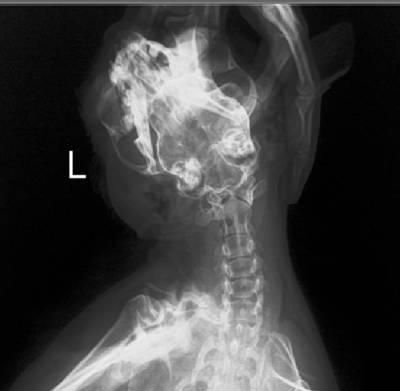

Абсцесс щеки у кошки - рентген

Выкладываю результаты рентгена (абсцесс на левой щеке). Может быть, что-то подскажете по снимкам?..

Снимок 2

Снимок 3

Снимок 4

Снимок 5

на 2м снимке в области корней 3го премоляра есть область пониженной рентгеноконтрастности, думаю причина ваших рецедивирующих абсцессов в гнилом зубе, если на нём большие отложения зубного камня и не приятный запах, то говорить об этом можно практически со 100% уверенностью.

Врач подозревает новообразование в кости...

Вот снимки в чуть лучшем качестве.

снимок